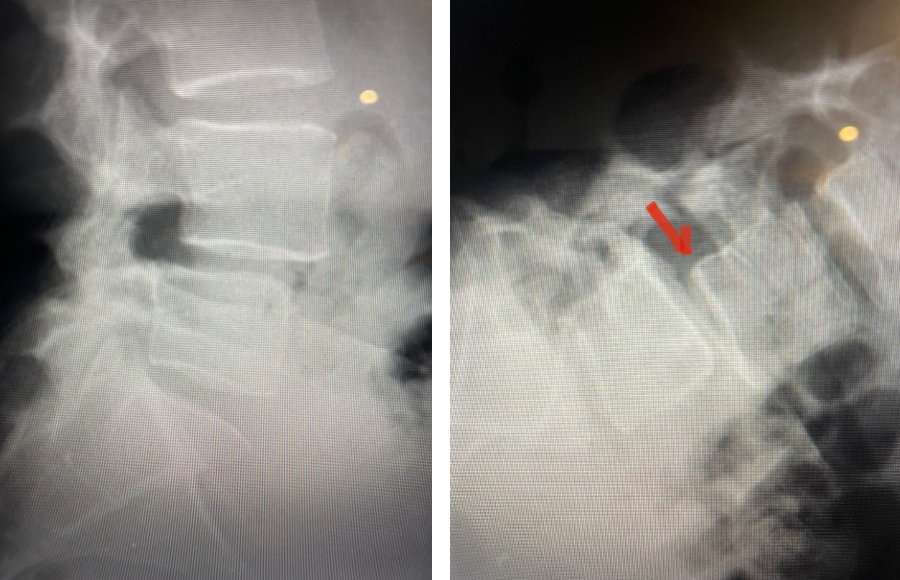

Fig 1: Plain X-rays demonstrating a grade 1 L45 spondylolisthesis with dynamic translation of approximately 4 mm (arrow).

Plain lumbar x-rays were done with flexion/extension views. Surprisingly the patient had 4 mm of anterior translation and slight angulation in flexion (Fig 1). This was unexpected because in degenerative spondylolisthesis the patient more commonly has auto stabilized by formation of stabilizing arthritic structures and has no motion on dynamic x-rays. However, approximately 20% of patients will have some degree of translation on flexion-extension x-rays with degenerative L4-5 spondylolisthesis. Because she had failed all means of conservative management, it was felt that the patient would benefit by a lumbar decompression and instrumented fusion because of the acute instability demonstrated on x-rays and her age.